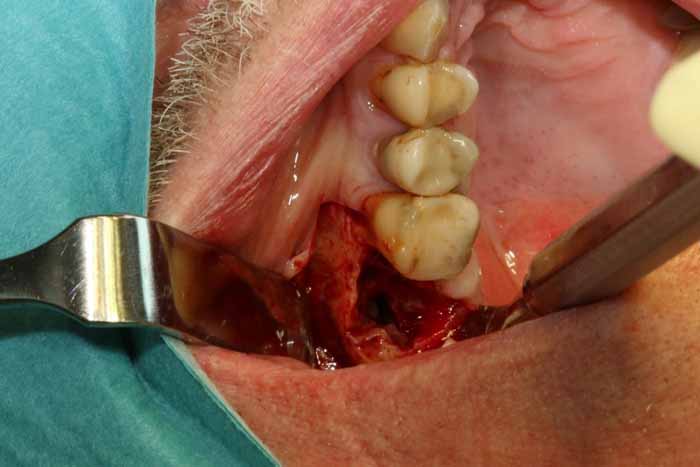

原因

上顎小臼歯と大臼歯の歯根は副鼻腔底に近くにあり、根尖性歯周炎では骨の境界が緩み、細菌が上顎腔に侵入して副鼻腔炎を引き起こす可能性があります。抜歯、顎外科手術、インプラント埋入では、口腔と上顎洞の間に急性的な交通路が残ることがあります。その結果、いわゆる口腔前庭部に口腔上顎洞瘻を形成し、そこから膿が排出され、それが副鼻腔への微生物の侵入点となり、細菌の定着や感染につながる可能性があります(画像2a、2b)。

治療

慢性副鼻腔炎の治療には、歯の感染の除去が含まれます。これには、歯内療法、歯周治療、または外科的な処置による抜歯が必要になる場合があります。感染の予防が困難な場合は、抜歯が必要になる場合があります。その後、副鼻腔の交通を特定するために、Vamevalテストを実施する必要があります。患者との良好なコミュニケーションが極めて重要であり、治癒を確実にするためには、より根本的な治療が必要になる場合が多いです。急性副鼻腔炎の場合は治療が必要です。PC予防と、ネザリルなどの充血除去薬を組み合わせた、1回限りの手術が行われる。より大きな交通や瘻孔が慢性化している場合は、鼻の矯正手術(画像4a~4e)が必要となります。場合によっては、耳鼻咽喉科医によるFESS手術と同時に行うこともできます。FESS手術では、鼻の側壁にある開口部を外科的に広げて換気を確保し、閉塞を防止します。

歯が原因となって菌の活動が活発になっていると思われる副鼻腔炎(保健センター/耳鼻咽喉科クリニックでのCT検査によって確認されたものなど)の場合、抜歯前に綿密な治療計画を立てる必要があります。抜歯後の副鼻腔閉鎖時に、副鼻腔内にまだ膿性浸出物が残っており、活動性の感染症がある場合には、交通路の形成が優れた技術的品質で実施されたとしても治癒の条件は悪くなります。副鼻腔閉鎖時には、感染を軽減し、副鼻腔から膿性浸出物を除去する必要があります。これは、抜歯3日前に抗生物質治療を開始することで達成できます。抜歯中は、患者が座った状態で鼻/口から透明な液体だけが出てくるまで、生理食塩水で副鼻腔を洗浄します。

その後、高品質の副鼻腔手術を行うことができ、口腔上顎洞瘻が生じることなく、治癒するための条件が改善されています。